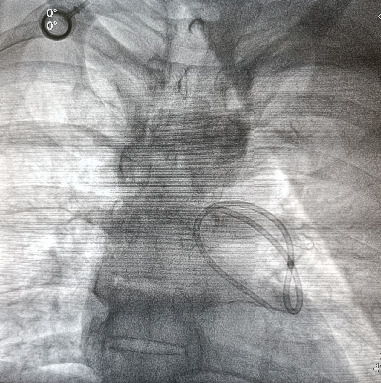

植入式皮下化疗孔是肿瘤化疗的常规载体。自发的导管脱位和导管栓塞是手术中罕见的并发症。在此,我们报告我们的经验,病人表现为自发性脱位和导管迁移到肺动脉。家族性腺瘤性息肉病合并右结肠腺癌患者行全直结肠切除术,经颈内静脉放置化疗孔,进行FOLFOX辅助化疗。被夹住的导管由介入心脏病专家通过经皮回收成功处理。

Implantable subcutaneous chemoports are routinely employed for delivering chemotherapy in oncology. Spontaneous catheter dislodgement and embolization of the catheters are rare complications of the procedure. Herein, we report our experience with a patient presenting with spontaneous dislodgement and migration of the catheter to the pulmonary artery. The patient having familial adenomatous polyposis with adenocarcinoma of the right colon underwent total proctocolectomy and had placement of the chemoport through the internal jugular vein for adjuvant FOLFOX chemotherapy. The entrapped catheter was successfully managed by percutaneous retrieval by an interventional cardiologist.